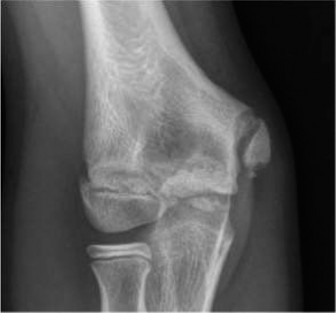

CASE 2 A 6-year-old boy fell from the monkey bars a few hours ago and had imme…